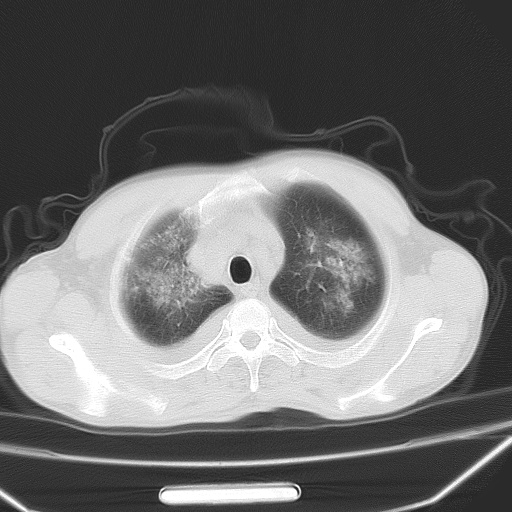

男、42岁、咯血3天。既往有甲亢、贫血、血尿蛋白尿史多年。血象:wbc:6.   中性粒:70.6%。

双肺野对称性磨玻璃影,分布于内中带,双侧胸水,患者有咯血。

双肺野广泛对称性磨玻璃影、实变影,以肺门为中心,主要分布于内中带,符合典型肺泡性肺水肿;伴双侧胸腔少量游离积液。结合患者既往病史且咯血就诊,支持多因素(尿毒症等)所致之肺水肿、肺出血、胸水;影像表现暂不考虑心源性水肿,且症状也不太符。需密切随诊结合临床治疗等进一步明确。